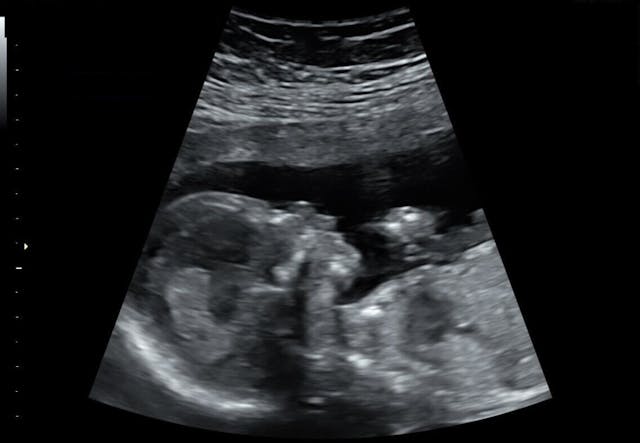

Fast forward to our ultrasound: we went in and saw our beautiful baby girl on the screen, moving around and sucking her thumb, and after a long analysis the doctors assured us that all looked to be well, but they couldn’t be 100% sure without an amniocentesis.